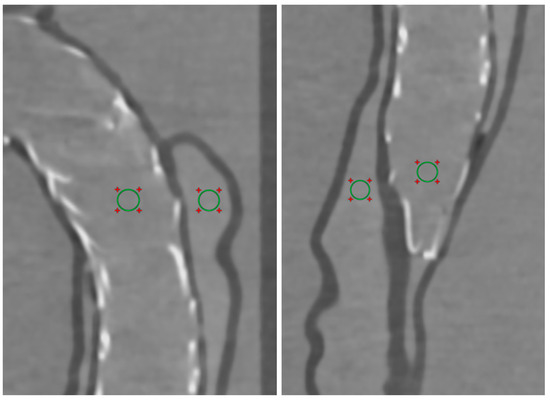

2.5. Quantitative Assessment of Image Quality